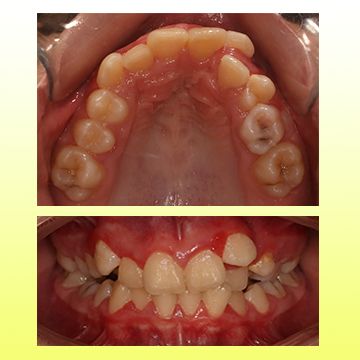

نمونه درمان ارتودنسی کودکان

تو سن 8 سالگی با مشکل بیرون زدگی فک پایین و عقب بودن فک بالا مراجعه کرد. تحت درمان پیچ باز کننده فک بالا و فیس ماسک، مشکل فک کاملا درمان شد. بعد اون با ارتودنسی ثابت درمانش تکمیل شد.